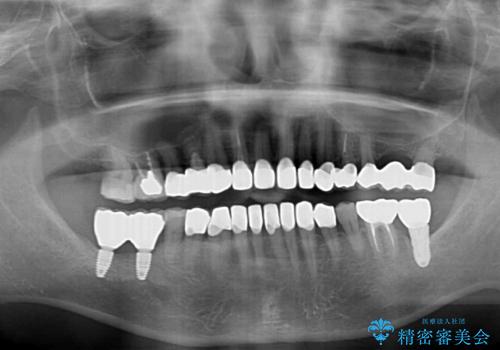

- 60歳を越え、黄ばんだ前歯をセラミッククラウンできれいな口元にしたいとのことで来院された患者様です。

診察したところ、前歯は反対咬合であり、その影響で抜歯が必要な奥歯があることが分かりました。

抜歯が必要な奥歯は、インプラント並びにブリッジにより補綴を行い、上下前歯は反対咬合を改善させるように補綴治療を行うこととしました。

健全な歯を削ってセラミッククラウンに置き換えることは、本来避けるべき治療と考えますが、今回は①患者様が60歳を越えていること、②要改善の咬合により抜歯が必要な奥歯があること、③反対咬合の前歯改善の手段としてセラミック治療が選択肢にあることなどから、全顎的なセラミック治療を行うこととしました。